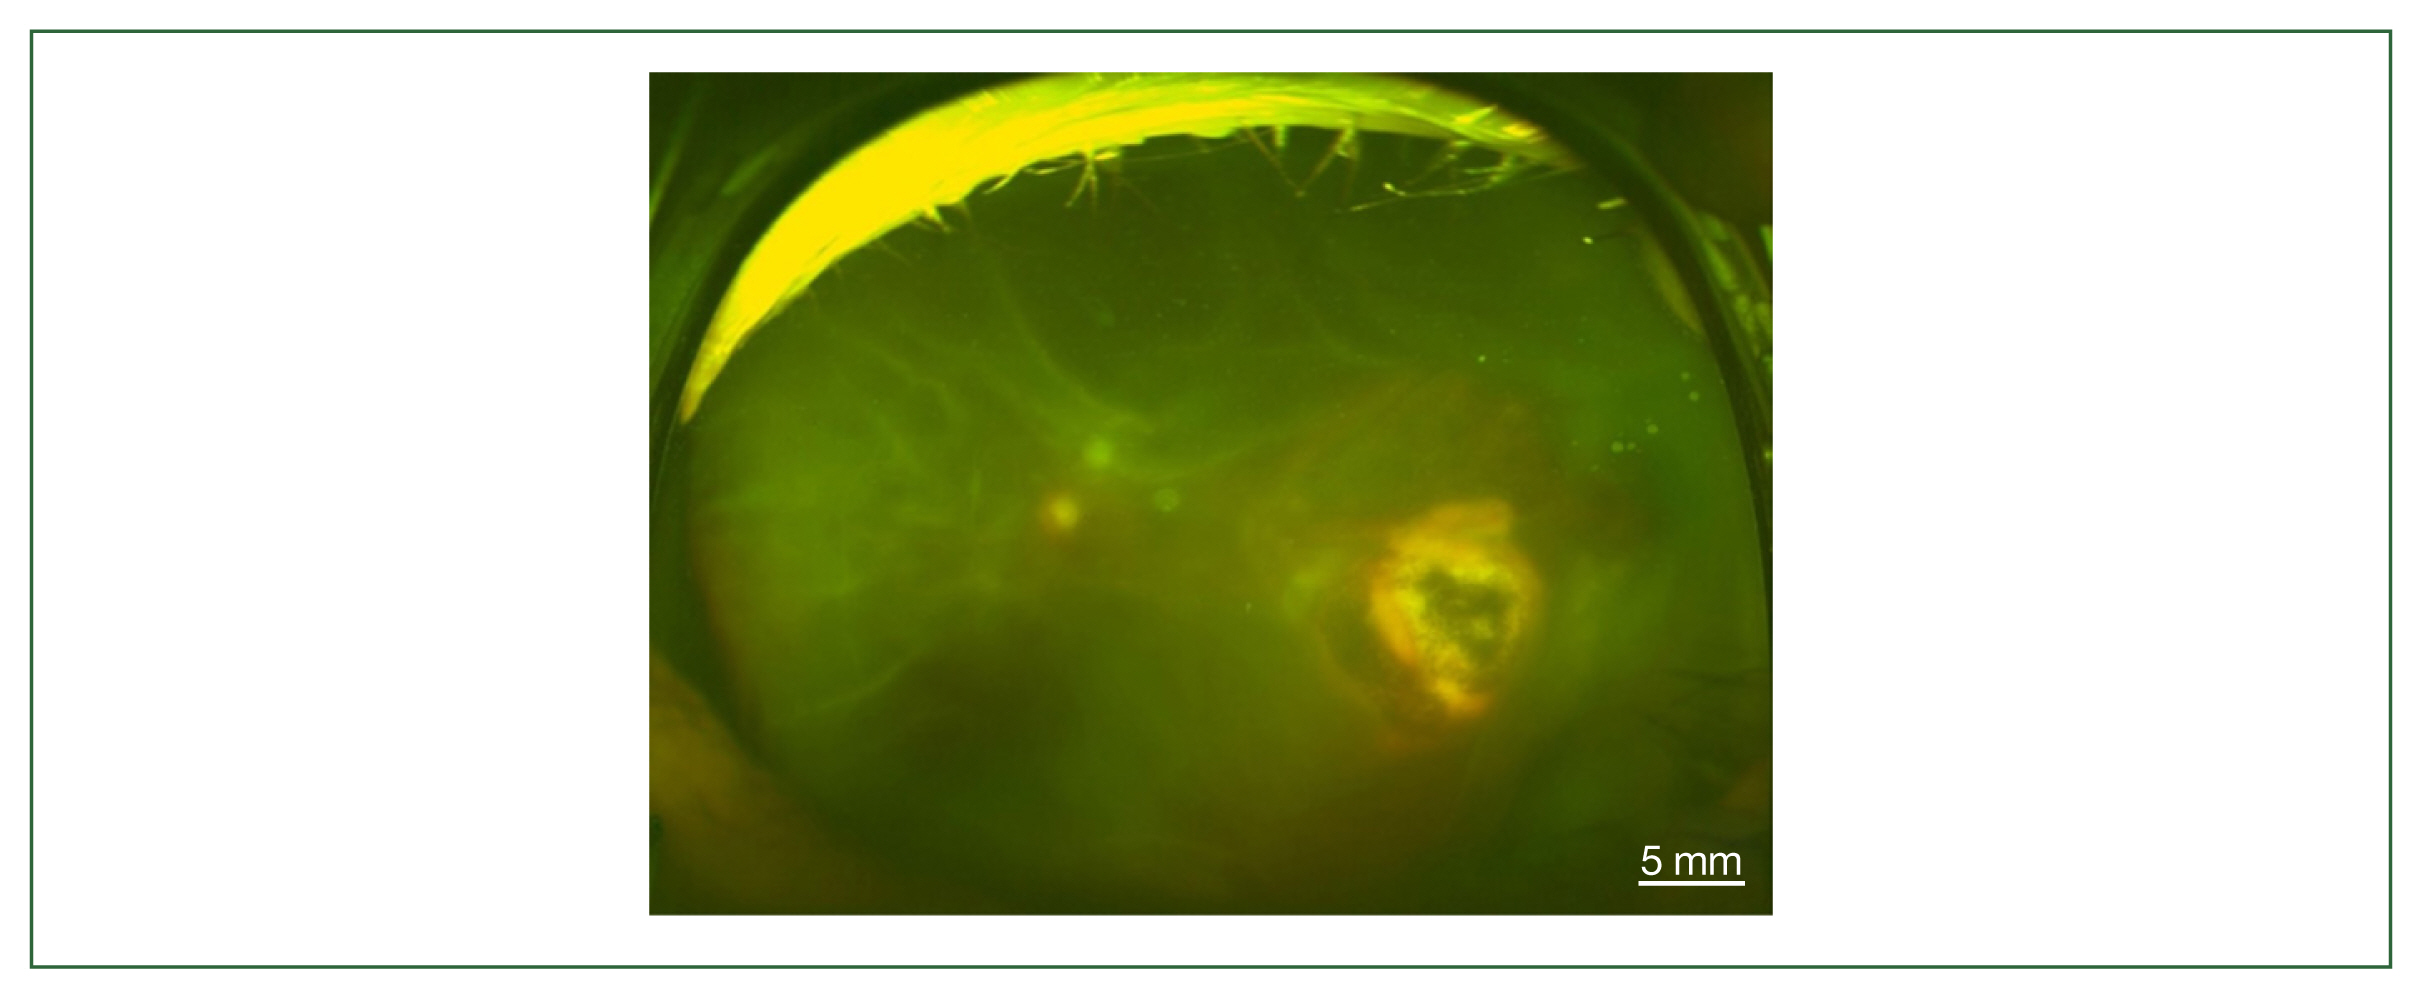

Fig. 3

Fundus photography of total retinal detachment associated with active ocular toxoplasmosis (left eye of case 3).

The 4 patients presented persistent unilateral visual disturbance 2–3 months before assessment. The ocular examination revealed that all study patients also exhibited unilateral panuveitis. Two patients (cases 1 and 2) did not show signs of chorioretinal scars, while the other 2 patients (cases 3 and 4) had preexisting scars on the retina and choroid. All of them showed an initial decimal visual acuity between 0.1 and 0.5. The ophthalmic analysis also revealed active retinochoroiditis in the 4 patients (Fig. 1) and papillitis and periphlebitis in cases 1 and 4, which were more evident by fundus fluorescein angiography (Fig. 2). All study patients also exhibited vitritis and anterior uveitis. Three patients (cases 1, 3, and 4) who underwent vitrectomy for diagnostic and therapeutic reasons had negative cytology for lymphoma cells. The remaining patient (case 3) had re-vitrectomy combined with scleral encircling for total retinal detachments developed later (Fig. 3). Only 1 patient (case 1), who was previously diagnosed with acute retinal necrosis (ARN) in a local ophthalmology clinic, received a systemic steroid treatment (60 mg per day) for posterior uveitis before visiting the Eye Center at the Seoul St. Mary Hospital, Catholic University. None had received any medication (including antibiotics) before the examination.